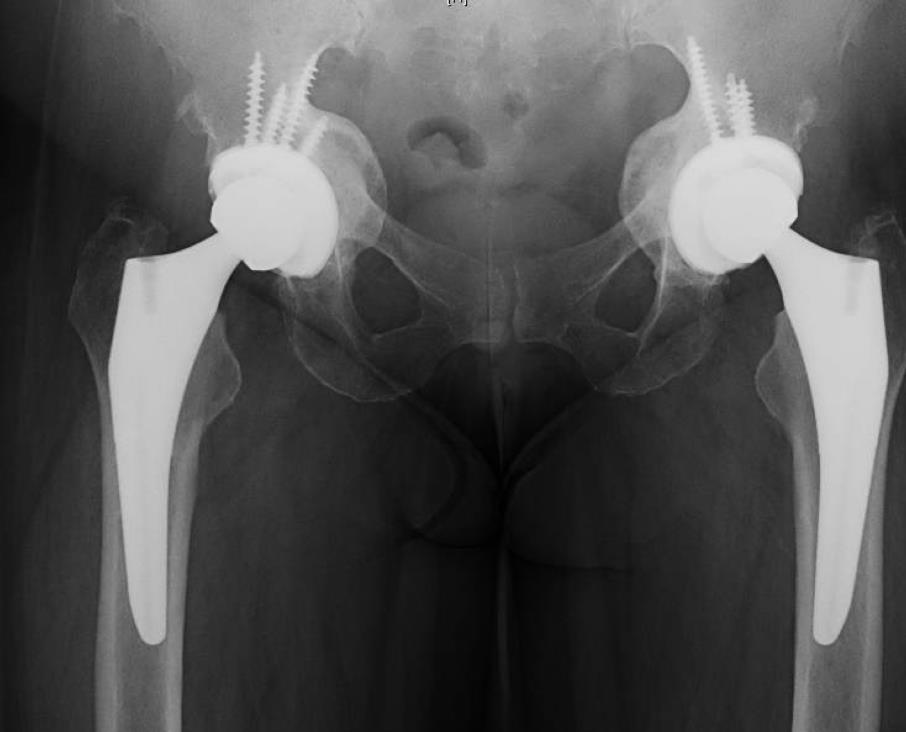

• Acetabular protrusio, or arthrokatadysis, is a rare osteological condition that may be primary (idiopathic) or secondary to other causes such as infectious, inflammatory, metabolic, traumatic, or genetic etiologies, leading to protrusion of the acetabulum and femoral head into the pelvis

• Diagnosis is made by a lateral center edge angle greater than 40 degrees or protrusion of the medial wall of the acetabulum past the ilioischial line (by 3 mm in men or 6 mm in women)

• Total Hip Arthroplasty (THA) is frequently employed for adult patients with acetabular protrusio and end-stage osteoarthritis, though it requires specific consideration of the patient's abnormal anatomy

• THA

• requires careful planning and adjuvants to address specific concerns in this patient population

• goals of surgery

• address medial or supero-medial migration of the femoral head

• address the altered abductor lever arm

• center of rotation may be determined by Ranawat's triangle method

• address the insufficient medial acetabular wall

• hip center of rotation

• requires restoration of a more inferior and lateral hip socket

• deviation of prosthesis center of rotation leads to a 24% increase in aseptic cup revision risk for every 1 mm deviation from native center of rotation

• acetabular socket preparation

• ream anterosuperiorly and posteroinferiorly, but not medially

• graft may be used to address acetabular defects

• recommended in cases of protrusion > 5 mm with a thin medial wall

• implants

• cementless cup